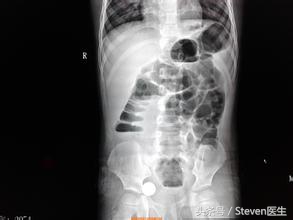

(2)辅助检查:X线立位腹平片检查:梗阻发生后的4~6小时,腹平片上即可见胀气的肠袢及多数气液平面。如立位腹平片表现为一位置固定的咖啡豆样积气影,应警惕有肠绞窄的存在;腹部CT针对发现腹部肠管扩张情况、腹水情况及肠管血供情况非常重要,必要时建议检查。

(2)辅助检查:X线立位腹平片表现为固定孤立的肠襻,呈咖啡豆状,假肿瘤状及花瓣状,且肠间隙增宽;腹部CT检查可看到腹腔内固定孤立肠襻,扩张肠管肠壁缺血、腹腔积液等,肠扭转的患者还可以看到肠系膜血管的“漩涡征”,CT检查针对发现梗阻的病因有较大意义。